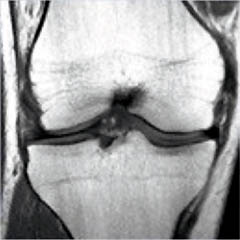

The Prostate without an Endorectal Probe |

The Heart |

![]() |

| Prostate: Delineation of Peripheral Zones (PZ), Cortical Zone (CZ) and Vescicles without an Endorectal Coil. | |

Figure 8.

Figure 8a-8d.

Further examples of the exceptional anatomic detail

made visible by the DISCOVERY

of Damadian of the pronounced differences in the decay

rates (relaxations) of the NMR signals

of the body's normal tissues (Figure

6). The DISCOVERED

differences supply the pixel amplitude differences

"PIXEL CONTRAST (IMAGE DETAIL)"

that produce, for the first time in medical history,

the detailed visualization of normal human anatomy

MRI is noted for. Note the visualization of the

vestibular and cochlear nerves

WITHIN

the internal auditory canel (Figure 8b) and the visualization

of the hypothalamic

tract (that transports hormones from

the brain) WITHIN

the pituitary stalk. (Figure 8c)